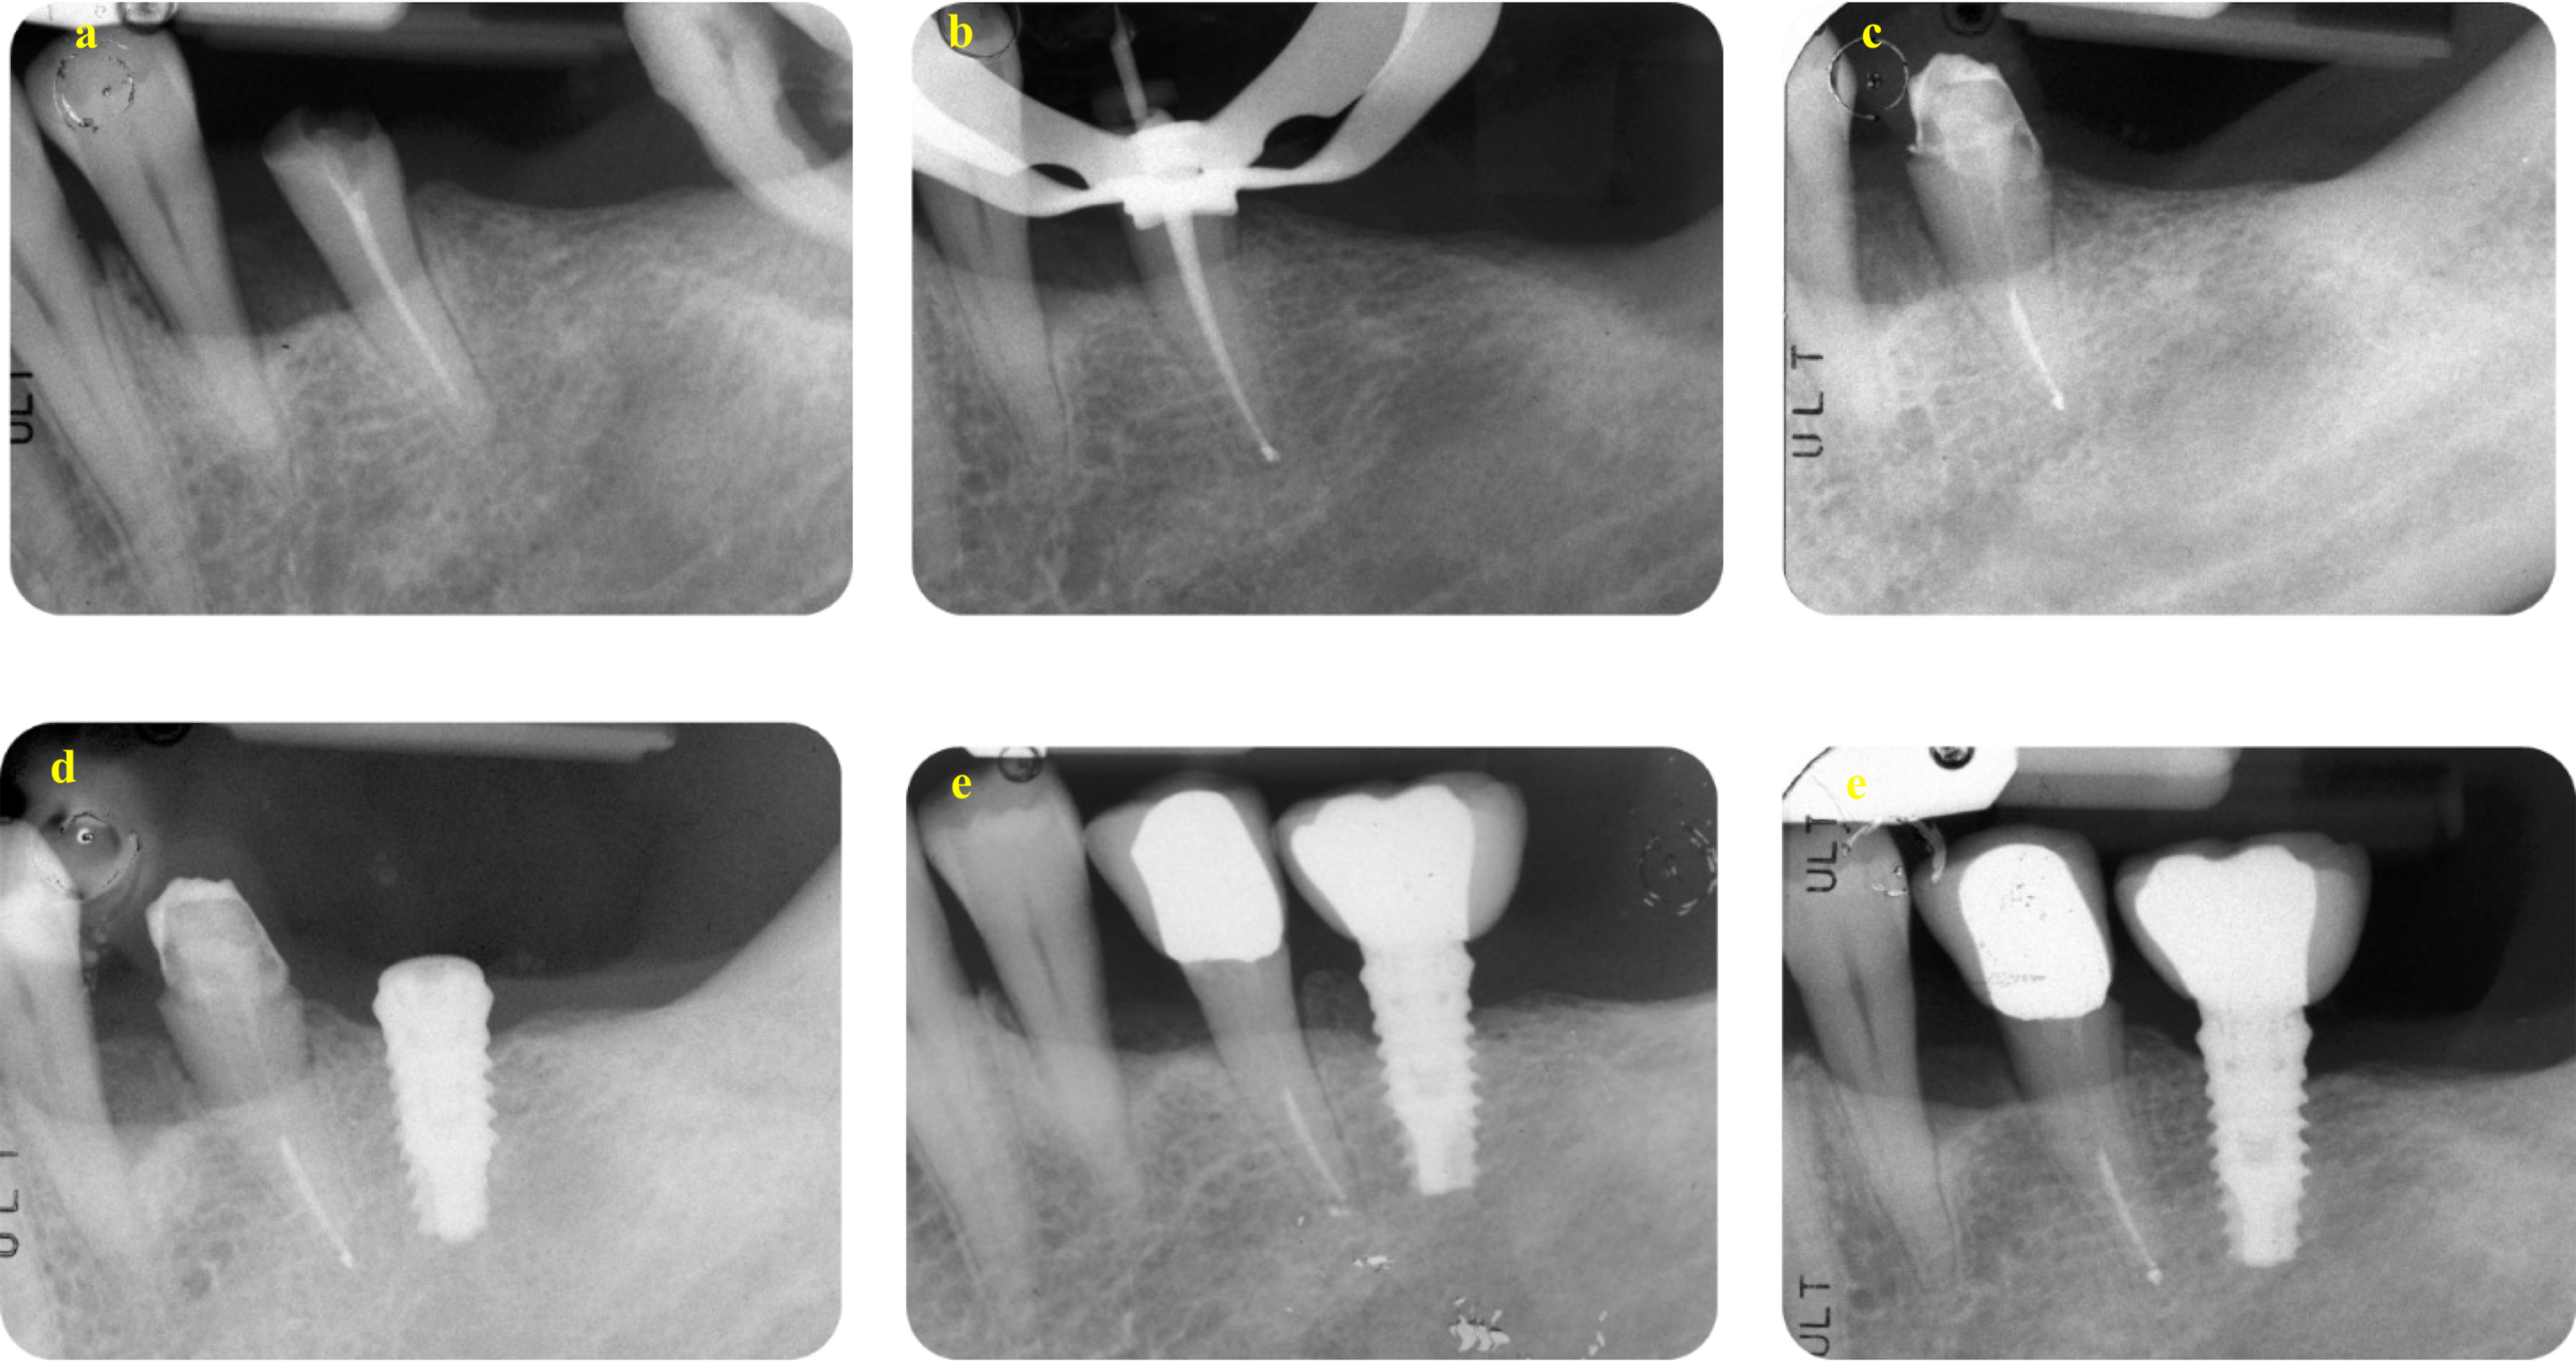

The distribution of MBL classes is presented in Table 7. Among the 56 implants, mean MBL at four years was 0.95 mm (95% CI 0.82 to 1.09) and 1.25 mm at eight years (95% CI 1.09 to 1.40), respectively, with a statistically significant MBL increase of 0.29 mm (95% CI 0.19 to 0.40, P-value < 0.001). Representative cases of teeth included in the study with an 8-year follow-up are shown in Figs. 4 and 5.

Fig. 5

A representative case of the Implant group. (a) The DM-Score was − 5 and suggested an extraction and implant placement. Score was calculated as follows: 2 residual (non-infiltrated) walls (-4), deep carious lesion (-2), CEJ MBL distance was less than 3 mm (+ 3), initial PAI was 2 (-2) and no presence of a preoperative post (+ 2). (b) Extraction was performed and early implant insertion was scheduled due to the presence of a periapical infection. (c) A cemented-retained Maryland bridge had been positioned as “interim prosthesis” for all the healing period. (d) After 3 months a customised abutment and a provisional crown was positioned. (e) After 28 days, a definitive metal ceramic crown was cemented. (f) Periapical radiographs after 8 years showed MBL stability